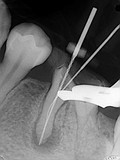

症例 2. 石灰化ケース

虫歯治療で歯の神経を保存する為に3ミックスMP法を使用したがその後痛みがでたため根管治療を開始したが、根管が石灰化を起こしており根管が確認できないということでご紹介された症例。

このような場合は歯科用CTを撮影し根管の確認を術前に行います。

治療中